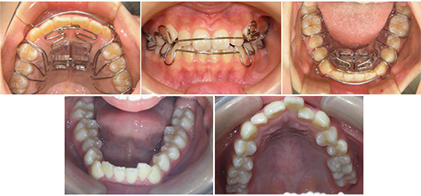

SH療法で使用する装置=SHA(SHアプライアンス)

SHA(SH療法で使用される装置について)ドイツと日本にて特許を取得したSlidexという弾性のバネを使用した新しい顎拡大装置です。

このSHAの取り扱いは、SHTA(Star Hill Therapy Association)会員のみが使用を許可されており、専門の技工部門(チーム)が行っております。

どこの医院、どこの技工所でも取り扱えることはできません。